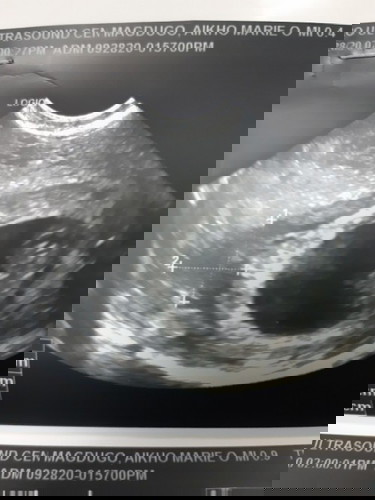

Sino po lagi ngsspotting until 18wks? Kase sa case ko on and off spotting ko kahit naka complete bedrest naman ako. Usually pag gising ko ng umaga 1st ihi ko pagka wipe ko meron sya brown or pinkish blood. Nag 2x a day na nga ako ng pangpakapit ni OB, taz normal naman lahat check ups ko and ultrasound. Hay nakoo #firstbaby #1stimemom

Just this morning po may lumabas na watery may kasamang spotting. Umiinom naman po ako ng pampakapit since 6weeks pa and bedrest po ako almost a mnth na. Sabi ni doc continue lang ng mga meds. Worried lang kase ako. May miscarriage history po kase ako. Laban and kapit lang baby 🙏 #1sttimeMommyhere